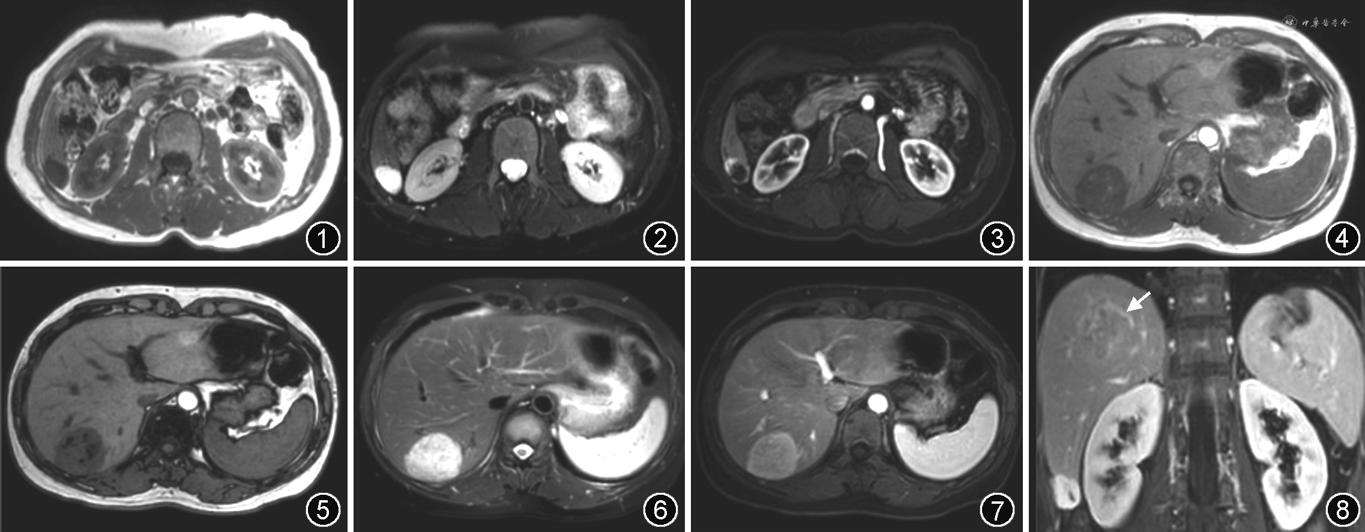

MRI上,T1WI为低信号,T2WI呈高信号,且随TE时间延长(>160 ms)信号逐渐增高,称之为“亮灯征”。DWI上呈高信号,但因存在T2透射效应,ADC值常无明显减低。巨大的海绵状血管瘤信号多不均匀,位于周边者可因纤维化而出现肝包膜皱缩。增强动脉期表现为周边强化,呈结节状、斑片状或环状,强化程度接近腹主动脉,随时间延迟向心性充填,表现为“快进慢出”(图1~3)。较小病灶也可表现为均匀强化,而较大病灶常不能完全充填对比剂。极少数病灶在增强各期强化均不明显,可能与窦腔狭小、富含纤维组织有关[4, 5, 6, 7]。

AML平扫信号多不均匀,T1WI呈高低混杂信号,T2WI呈不同程度的高信号。病灶内的血管在T1WI可呈流空信号,在T2WI多因慢血流而呈高信号。脂肪成分在T1WI、T2WI均呈高信号,在脂肪抑制序列上呈低信号。脂肪成分是准确诊断AML的关键,T1WI化学位移成像有助于检出少量脂肪。AML内含有大块脂肪组织成分,当含量较多时在T1WI反相位表现为周边环形信号衰减。除脂肪瘤型外,大多数AML是富血供的,增强动脉期实质部分呈明显不均匀强化。“中心血管影”是AML的特异征象,表现为明显强化的实质成分中有增多扭曲的小血管,特别是在脂肪成分中见到血管影更具诊断意义[10, 11, 12, 13, 14]。增强门静脉期及延迟期可持续强化,也可呈稍低信号,周边常见到迂曲扩张的引流静脉。肿瘤较大压迫周围肝实质时,可形成不完整的假包膜(图4~8)。